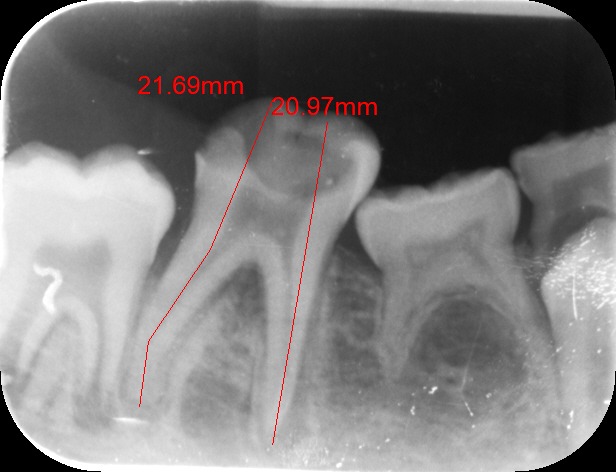

An access cavity is placed on the surface where the patient bites, to reach the root canals of the tooth. Once all the canals are identified, small files are used to remove the infected pulp.

Files of different sizes are used to eliminate bacteria and infection and to shape the canals. The canals are disinfected thoroughly with irrigants and later the canals will be sealed in 3 dimensions with a special medicament called gutta-percha to prevent reinfection of the tooth and the access cavity will be sealed with a temporary filling.